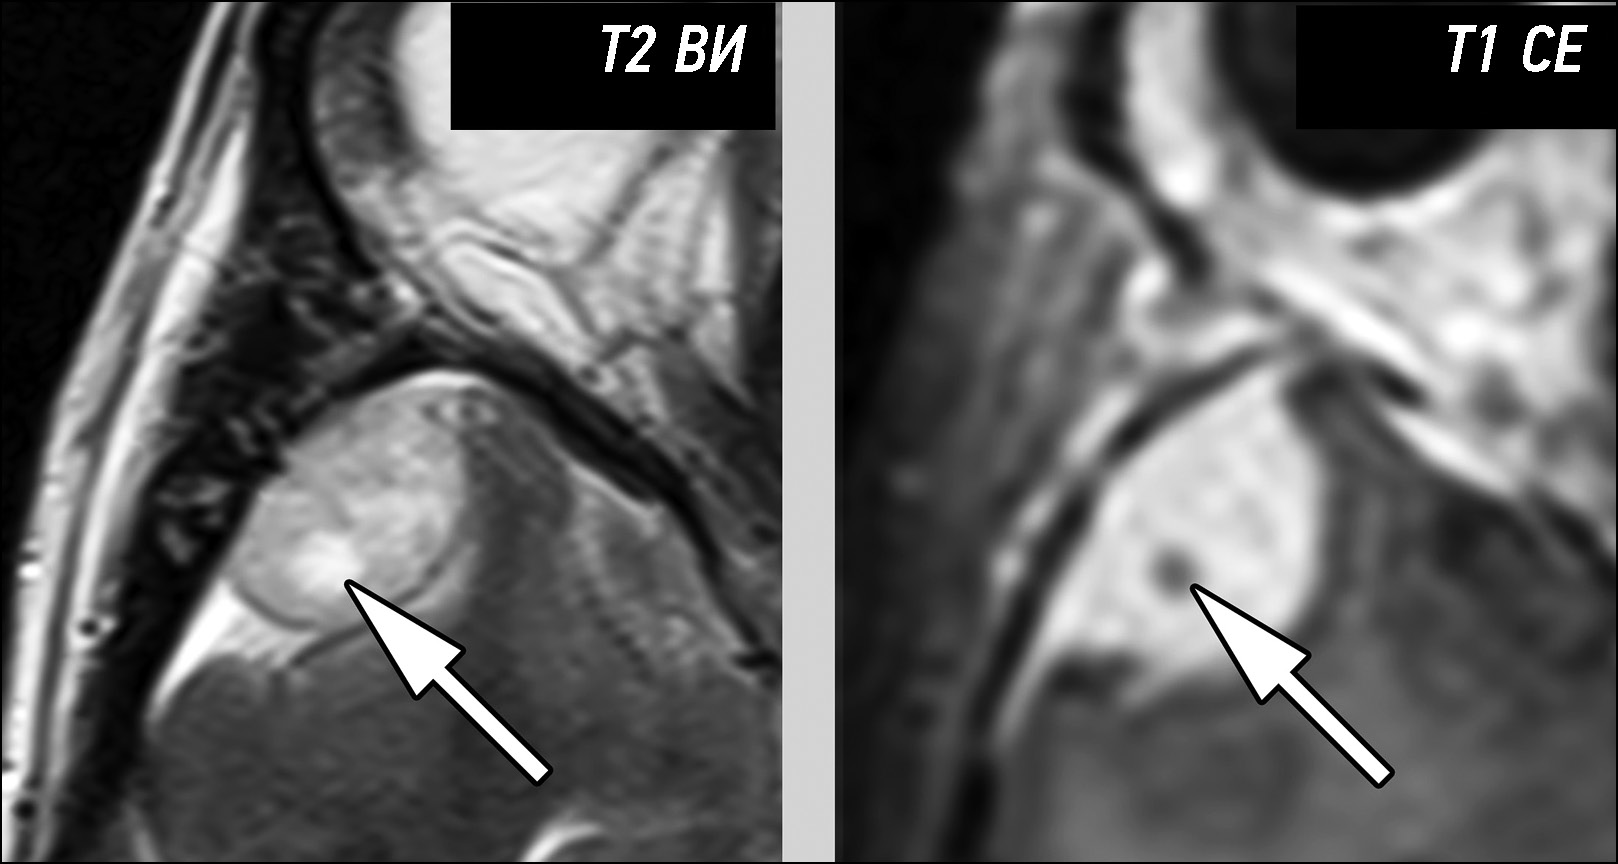

Первичные внемозговые опухоли представлены доброкачественными и злокачественными новообразованиями мозговых оболочек и черепных нервов. Их предоперационная дифференциальная диагностика основана на анализе семиотики магнитно-резонансной томографии. Критически важными моментами, позволяющими классифицировать опухоли данной группы, являются следующие признаки: структура образования, характер контрастирования, отграничение образования от мозговой ткани, наличие взаимосвязи с мозговыми оболочками или черепными нервами.

Провести дифференциальную диагностику различных типов первичных внемозговых опухолей на основе визуального анализа данных магнитно-резонансной томографии в большинстве случаев, при типичных признаках семиотики, не представляет затруднений. При атипичных проявлениях на магнитно-резонансной томографии надёжное разграничение опухолей бывает затруднительно. Наибольшую сложность при этом представляет дифференциация менингиом различной степени злокачественности, разграничение солитарных фиброзных опухолей и менингиом и установление типа опухоли при её локализации в мостомозжечковых углах.

Представлена серия наблюдений, содержащая наиболее типичные ситуации, приводящие к ошибкам дифференциальной диагностики первичных внемозговых опухолей на основании данных магнитно-резонансной томографии. Все представленные образования были верифицированы по результатам постоперационного гистологического исследования.

Анализ приведённых клинических примеров показывает, что рассмотрение всей совокупности признаков семиотики может уменьшить количество диагностических ошибок.